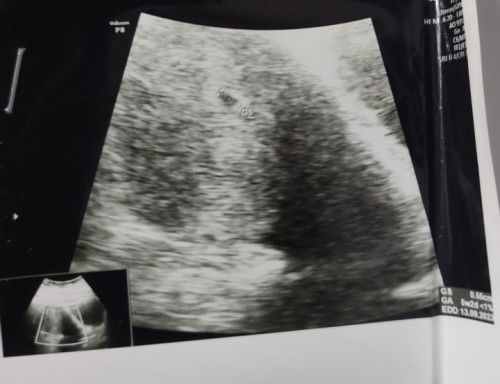

Hasil USG Obesitas

Bund, apa ada pengalaman yg sama obesitas hamil perkiraan 5-6 minggu hasil USG tidak jelas? USG di dokter A kelihatan kantung GS 0,55cm dan penebalan dinding rahim, sedangkan USG di dokter B tidak kelihatan apa2 katanya terlalu tebal. Jadi khawatir, ini kehamilan pertama setelah 7 bulan menikah 😞 Update: USG usia 10 minggu sudah terlihat janin dan ada detak jantungnya. Alhamdulillah 😊